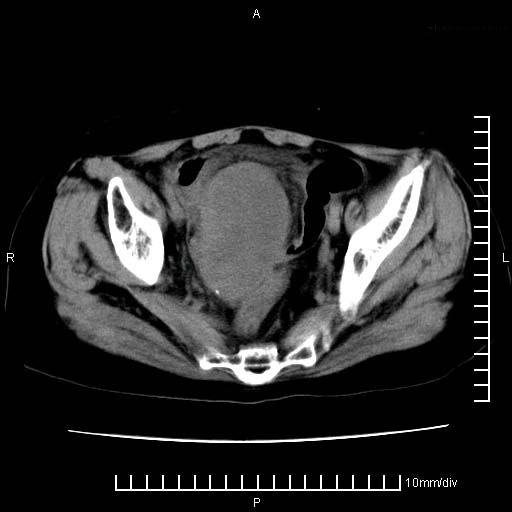

标题: CT24821:女性,70岁

下腹疼痛2月,加重并呕吐2天,下腹压痛,反跳痛。白细胞1万2.

下腹至盆腔较大包块,与邻近肠管关系密切,下腹疼痛2月,加重并呕吐2天,下腹压痛,反跳痛。白细胞1万2.

补充:道格拉斯腔内有积液,且密度较高,显然提示有感染。

有病理了,楼上的哥们你说对了

感谢楼主反馈术后病理结果(卵巢癌),学习了!